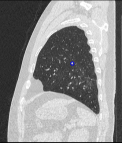

Chẩn đoán hình ảnh mô mềm tiên tiến cho vùng bụng.

Tăng cường độ tương phản I-ốt.

Hỗ trợ đánh giá an toàn cho bệnh nhân.

Đảm bảo hình ảnh chất lượng cao.